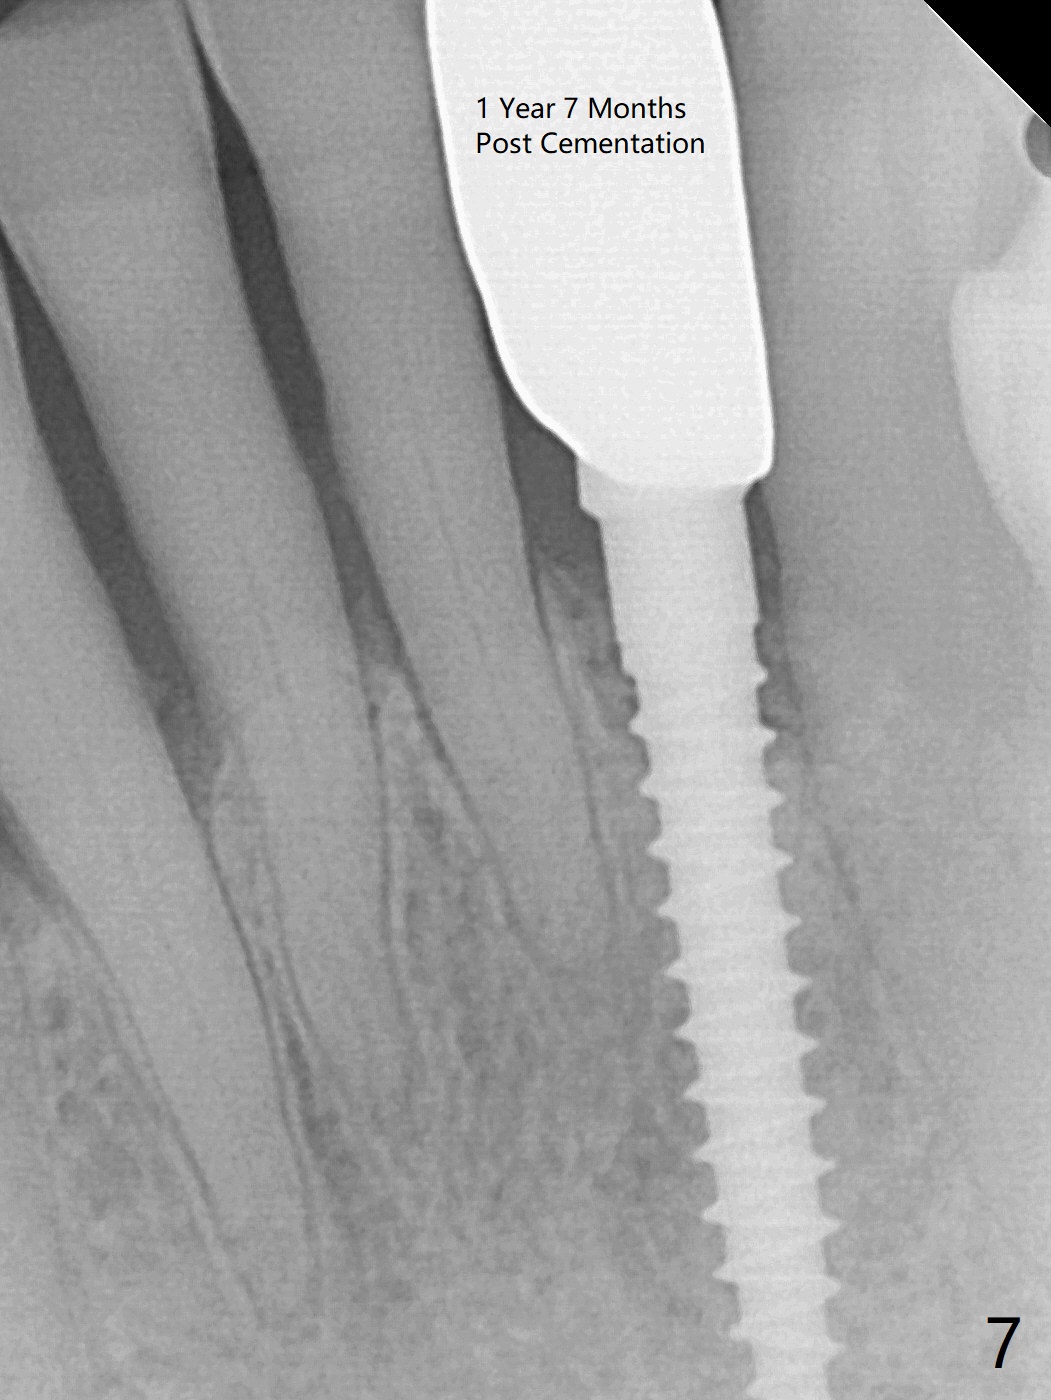

The tooth #23 is going to be extracted because the patient cannot masticate normally with mobility (Fit.1). The gingival depth is measured 2-4 mm after extraction. The 1st intraop PA taken with 1.2 mm drill for 16 mm shows the mesiodistal width is 5.11 mm (Fig.2); a 2.5x14(2) mm 1-piece implant is placed with >35 Ncm (Fig.3 with allograft placed). Following abutment preparation, an immediate provisional is fabricated to close the socket (Fig.4 P). There is no bone loss (Fig.5) or gingival inflammation (Fig.6 after reprep) 3 months postop. The narrow implant (2.5 or 2.0 mm) is indicated in the narrow edentulous space. The distal crest seems to be reduced in density and lower in height 1 year 7 months (Fig.7) and 1 year 11 months (Fig.8) post cementation. The severity does not worsen probably related to use of water pik. The crown looks bulky probably due to too large the abutment and too buccal placement of the implant (Fig.9, 10, as compared to Fig.1). A 2 mm implant may help?